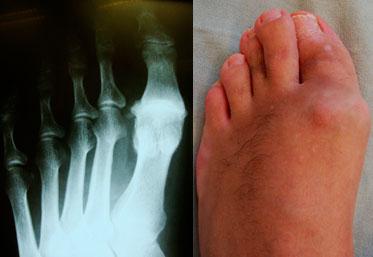

Вальгусная деформация (hallux valgus, халюс вальгус) представляет собой заболевание, которое затрагивает сустав на большом пальце ноги. На стопе формируется костный нарост, который легко заметен при проведении осмотра.

Термин «вальгусная деформация» происходит от латинского слова valgus, что переводится как отклонение от нормальной оси. Популярное название — шишка на большом пальце — весьма точно отражает самое заметное проявление данной патологии.

Вальгусная деформация — это шишка, образующаяся сбоку стопы или в области большого пальца. Причинами формирования данной патологии могут быть:

Существует четыре стадии этого состояния. На начальных этапах уплотнение минимально и не заметно, но со временем оно может увеличиться и стать серьезной проблемой. Начальные стадии можно контролировать с помощью специальных ортопедических стелек и правильного выбора обуви, но в более поздних стадиях может потребоваться хирургическое вмешательство.

Для коррекции вальгусной деформации первого пальца стопы применяются корригирующие остеотомии. Эти операции направлены на устранение деформации и сохранение функции сустава. Не достаточно просто удалить «шишку», необходимо провести коррекцию I плюсневой кости с фиксацией с помощью специальных винтов.

Дисбаланс сухожильно-мышечной структуры из-за падения сводов стопы приводит к отклонению первого пальца наружу (развивается вальгусное искривление, hallux valgus) и другим деформациям.

Изменение конфигурации сводов стопы и их ненадежность приводят к увеличению нагрузки на связочный аппарат и сухожилия, что, в свою очередь, может стать причиной артроза. Постоянное давление головок плюсневых костей на мягкие ткани вызывает метатарзалгию и способствовать образованию натоптышей.